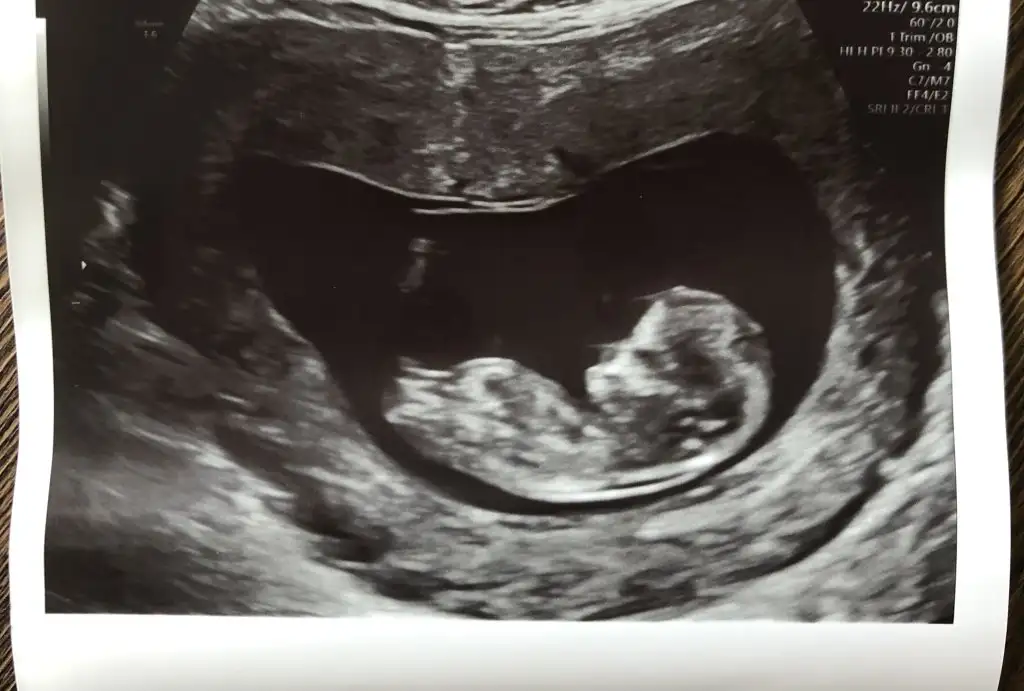

11 haftam doldu bu gün . Dün kontrolüm vardı. Daha bu kadar erken cinsiyet söyleyeceğini beklemiyordum ama doktorum oğlana benziyor dedi büyük ihtimal oğlan dedi. Ama tabi ileriki haftada daha da netleşir dedi. Özele gidiyorum ben de ama doktorum aldırmayacaksan ikili yapma dedi ki zaten ben de istemediğimi söyledim. Benden haberler böyle . Sık ye az ye dedi. Gaz İçin maden suyu içebilirsin dedi. Bakalım bi ay sonraya çağırdı tekrar 🥰

Bu arada doktor erkek tahmininde bulunmuş. 😇 ultrason fotoğrafı atmanız mümkün mü acaba? Bakabilir miyim? Ben de foto atmıştım erkek diyor bakanlar. 😊 doktor bir şey demedi henüz